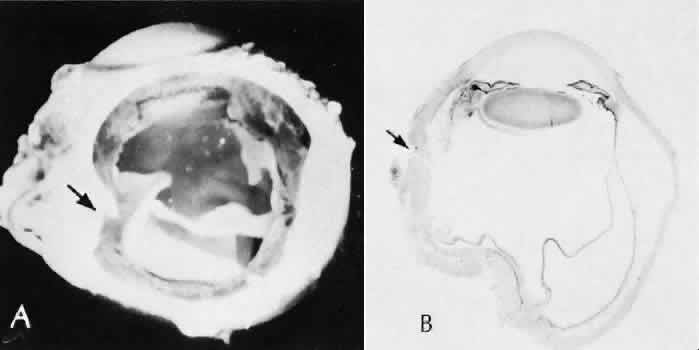

Expulsive choroidal hemorrhage (Fig. 30) is a rare catastrophic complication often resulting in total loss of the eye.93 The site of hemorrhage is probably a sclerotic choroidal arteriole where the vessel crosses the suprachoroidal space from the scleral canal. The sudden hypotension after surgical penetration of the globe causes a bending and then a rupture of the arteriole.94 Although most hemorrhages are massive and immediate, they occasionally are delayed, and some may not occur for days or weeks after surgery. Delayed choroidal hemorrhage may occur at the time of corneoscleral suture removal,95 because of clinically unapparent wound dehiscence or as a result of perforation of a corneal ulcer.

Fig. 30. A case of expulsive choroidal hemorrhage. A. Expulsive choroidal hemorrhage occurred 3 weeks after cataract surgery at the time when a limbal suture was removed. The intraocular pressure was reduced enough to allow shearing forces in the superficial choroid to tear an arteriole resulting in a high-pressure hemorrhage. B. In another case enucleated shortly after cataract extraction because of expulsive hemorrhage, accumulated blood can be identified in the suprachoroidal space. Because of the loose attachment of the choroid to the sclera, all intraocular contents were displaced toward the cataract wound. (Hematoxylin-eosin stain; × 3.)

Histologically, massive choroidal hemorrhagic detachment is associated with a retinal detachment. The retina and choroid may herniate through the scleral wound. A ruptured ciliary artery may be found in the suprachoroidal space.